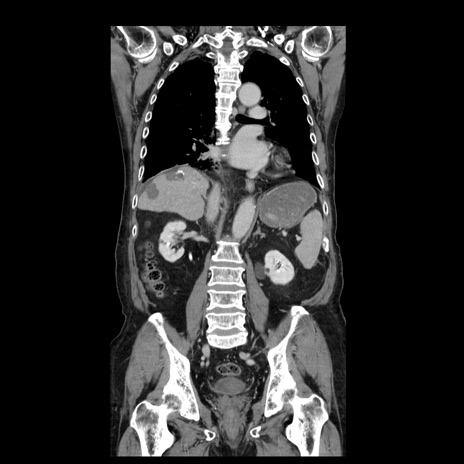

症例21(冠状断像)

【症例】70歳代男性

【主訴】腹痛

【現病歴】肝硬変・肝細胞癌にてかかりつけの方。約9時間前に食後より腹痛出現。症状が徐々に増悪し、嘔吐出現したため来院。

【既往歴】肝硬変、肝細胞癌(RFA、TACE後)

【身体所見】意識清明、表情苦悶様、BT 36℃、BP 129/78mmHg、P 88bpm、SpO2 97%(RA)、右上腹部から心窩部にかけて圧痛あり、反跳痛なし、筋性防御あり。

【データ】WBC 5800、CRP 0.16